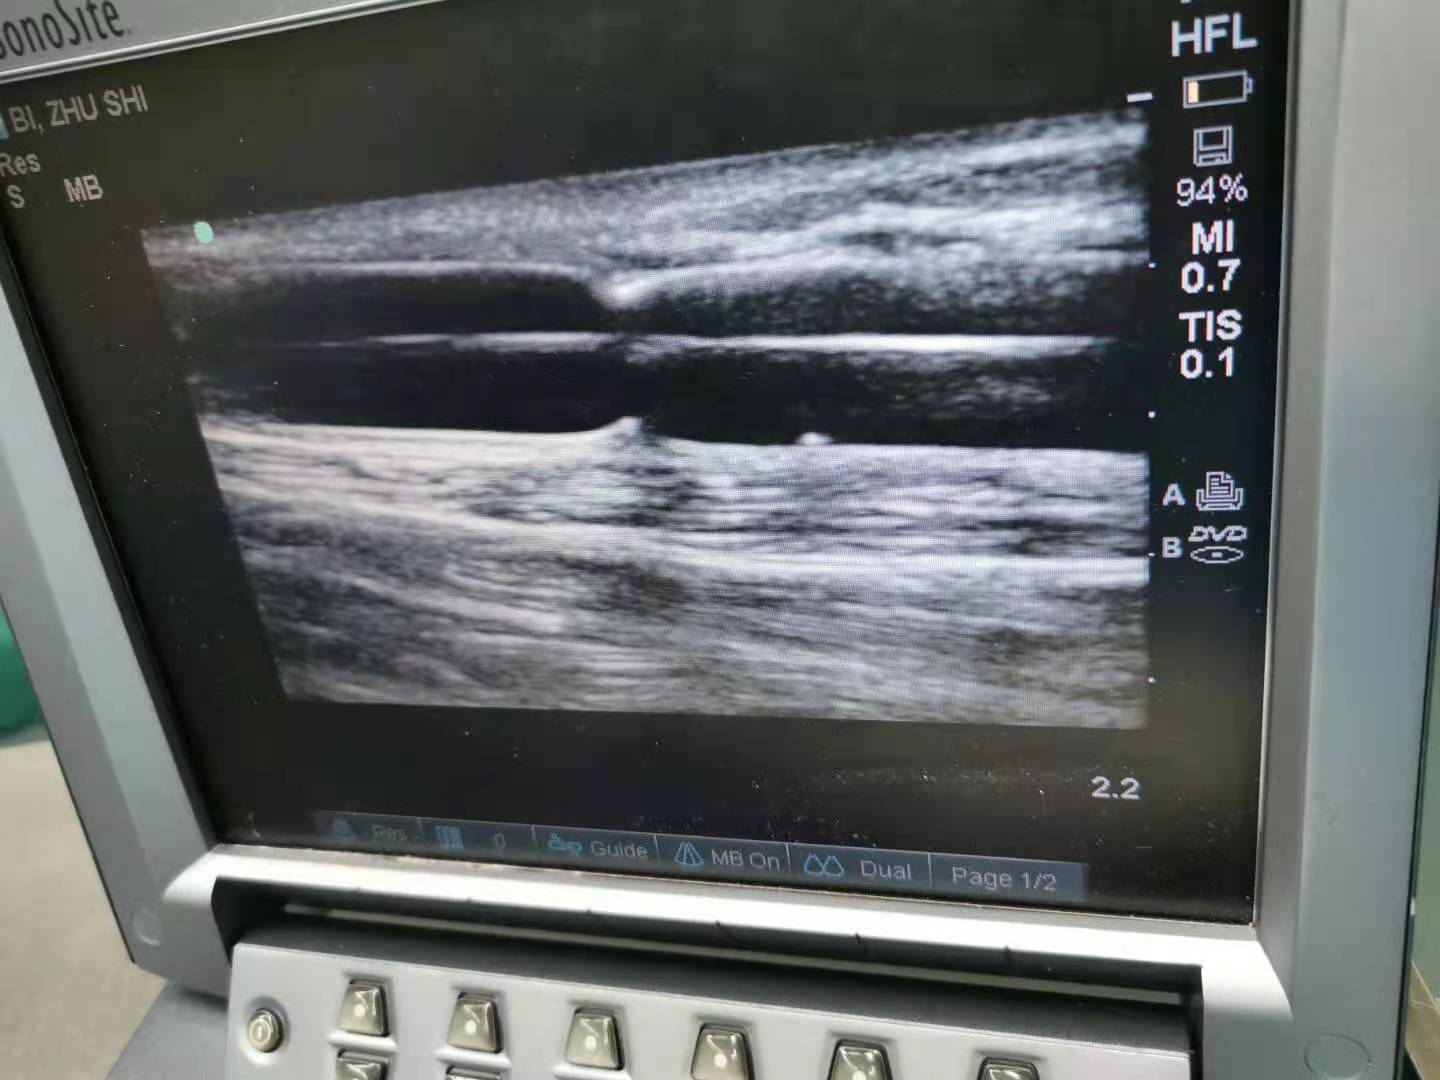

我科开展主要诊疗业务:急慢性肾炎、IgA肾病、急慢性肾功能衰竭、肾病综合征、糖尿病肾病、高血压肾病、多囊肾、系统性血管炎肾损害、蜂蛰伤及各种中毒类疾病。开展超声引导下肾活检穿刺术,开展自体动静脉内瘘成型术、自体动静脉内瘘血栓取出术、超声引导下动静脉内瘘球囊扩张成型术、DSA引导下动静脉内瘘球囊扩张成型术、DSA引导下带涤纶套皮下隧道式半永久导管置入术、带涤纶套皮下隧道式半永久导管拔出术。

超声引导下动静脉球囊扩张成型术